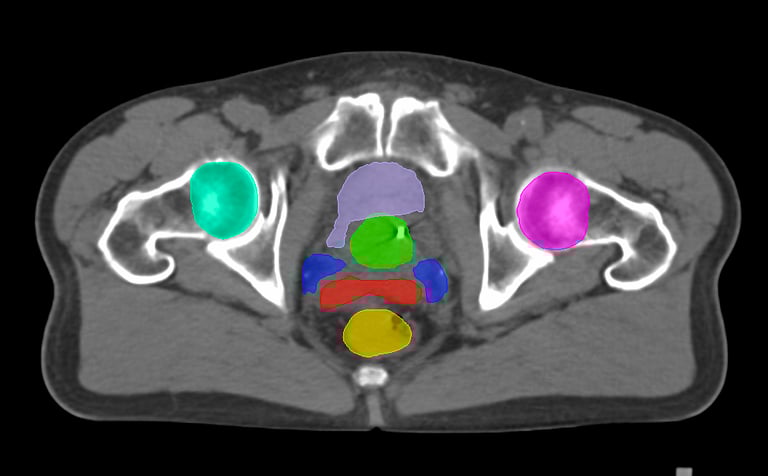

The DAM Contour features a comprehensive collection of OARs and CTVs that are ready for immediate use, without the need for manual creation of atlases or manual adjustment of data. This product includes all standard OAR and CTV structures (over 117 in total).

The Pelvis lymph node region encompasses lymph nodes that include the obturator lymph nodes, internal and external iliac lymph nodes (limited anteriorly at the level of the femoral heads), and extends up to the common iliac lymph nodes, covering the L5/S1 region.

Pelvis